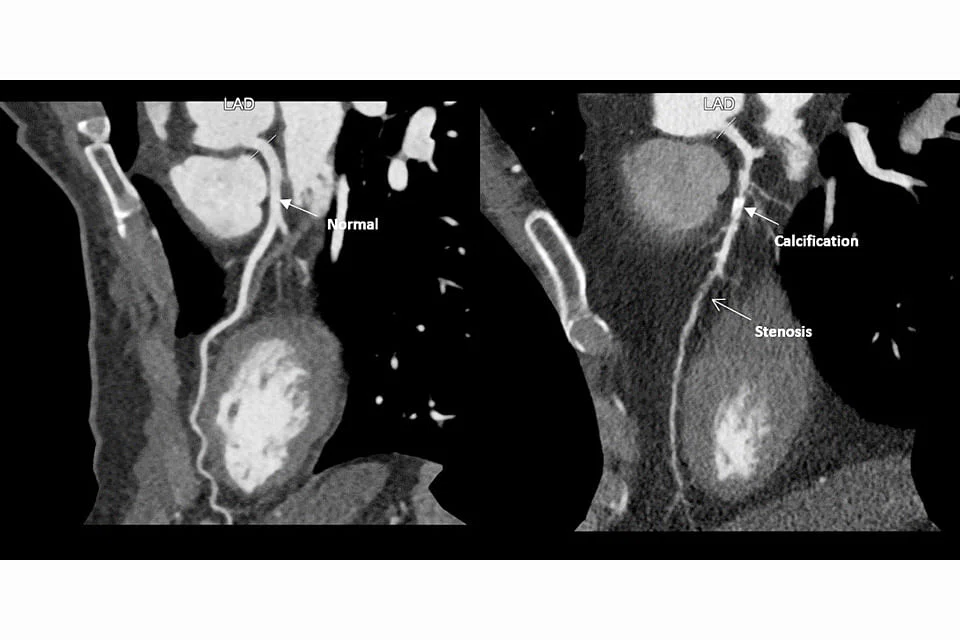

We do have the technology to detect significant disease. The statistics from stress ECG with the treadmill has a positive accuracy of 70 per cent and CT calcium score 95 per cent with a CT coronary angiogram, the negative predictive value of studies rises to 98 per cent, but accuracy diminishes when calcium score rises to more than 400.

In an article in 2010, it was commented that very limited information was available on the role of Coronary CT Angiogram for risk assessment in asymptomatic persons. The prevalence of significant coronary stenoses in the low-, moderate- and high-risk groups was 2 per cent, 7 per cent, and 16 per cent, respectively. The groups are stratified according to Global Risk Assessment tools based on age, gender, blood lipid profile, and major associated risk of hypertension, diabetes and smoking (eg Framingham Risk Assessment). Men are assessed to be at much higher risk, 2-5 times more than women.